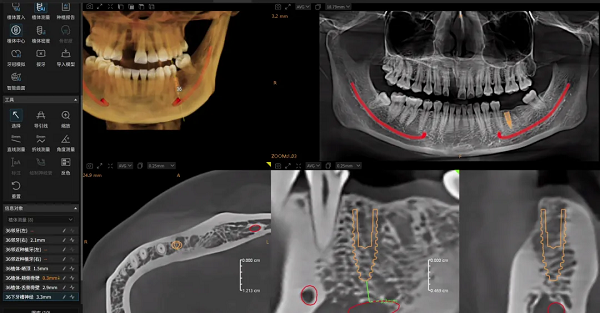

可靠的诊断始于清晰的影像。神农·云CT全新升级双能技术,能从物理层面有效识别并分离由金属植入物产生的伪影,显著降低其对周围关键解剖结构的干扰。

这项技术为种植规划提供了干净、可靠的影像基础,使医生能够清晰地辨识牙槽骨形态、骨小梁结构、神经管走向以及邻牙关系,将诊断依据从基础的“看得见”提升至精准的“看得准”,为后续每一步决策筑牢安全基石。

2.智能规划:从经验依赖到人机协同的进化

面对复杂手术规划,Dental X云平台能基于患者影像数据,由AI自动生成包含植入位置、角度和深度的三维规划方案。这不仅大幅缩短了规划时间,其科学性更为医生提供了可靠的参考基准,让医生能将核心精力集中于方案的个性化调整与优化,实现人机协同的决策模式。

当规划方案确认后,AI可一键生成与之精确匹配的手术导板,并支持椅旁3D打印,助力诊所构建“数据采集→诊断分析→方案设计→导板打印”的全流程数字化闭环。这一革新将传统流程平均3天耗时,大幅缩短至约1.5小时,真正实现了种植诊疗的效率和精准革命。

针对种植导板在复杂病例中的局限性,Dental X云平台创新性地实现了导板与导航的自由切换。术前规划数据可无缝对接至种植导航设备,实现术中实时引导与校准,确保即使在最复杂的解剖条件下,种植方案也能精准落地。

△ Dental X 可无缝接入种植导航